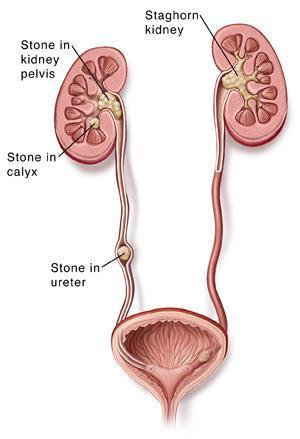

سنگ هاي کلیوي ذرات کوچک و سختی هستند که در یک یا در دو کلیه تشکیل شده و گاهی به داخل حالب ها ( لوله هاي عضلانی باریکی که ادرار را از کلیه ها به مثانه منتقل می کنند ) انتقال می یابند.

شناخت انواع سنگ ھای کلیه

سنگ کلیه شاخ گوزنی (stag horn)